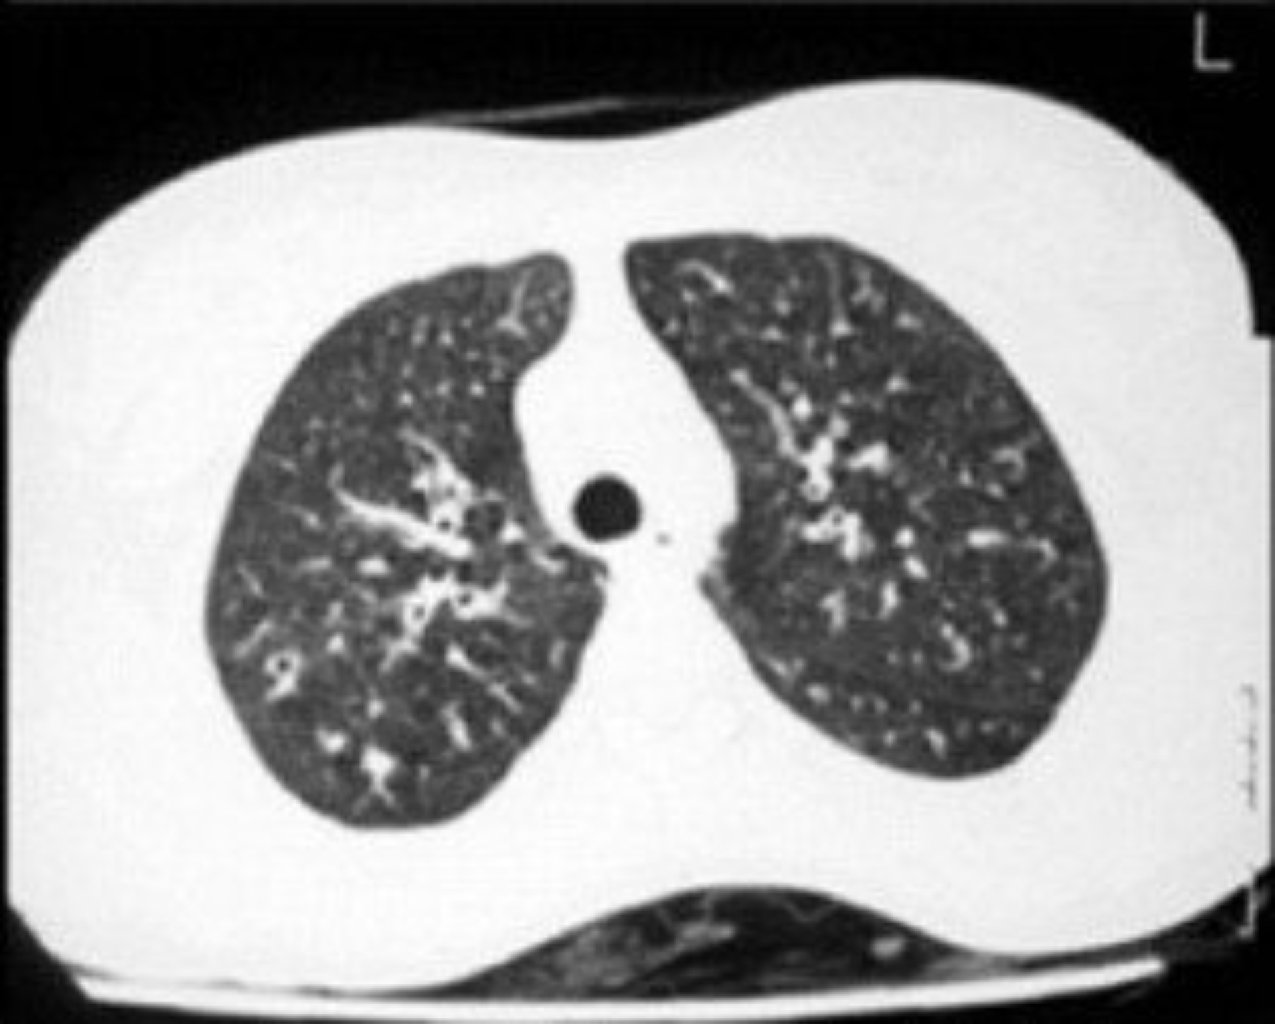

Bronşektazi

Bronşektaza səbəb olan bir çox faktor ola bilər. Onların arasında: Təkrarlanan tənəffüs yollarının i ...